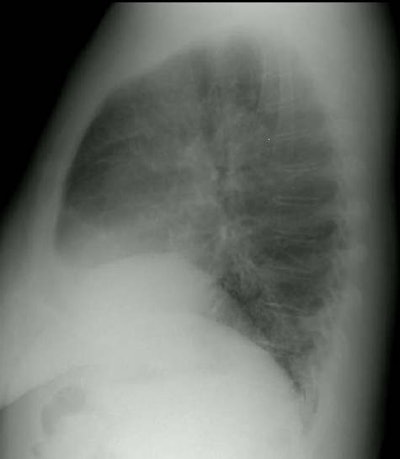

Interstitial Lung Disease in Rheumatoid Arthritis

The frontal and lateral views of the chest are from a patient with rheumatoid arthritis. The elevation of the right hemidiaphragm is a chronic finding in this patient. The films demonstrate a shaggy appearance to the heart border on the frontal examination and prominent interstitial markings are very evident over the spine on the lateral examination. See CT scan below.